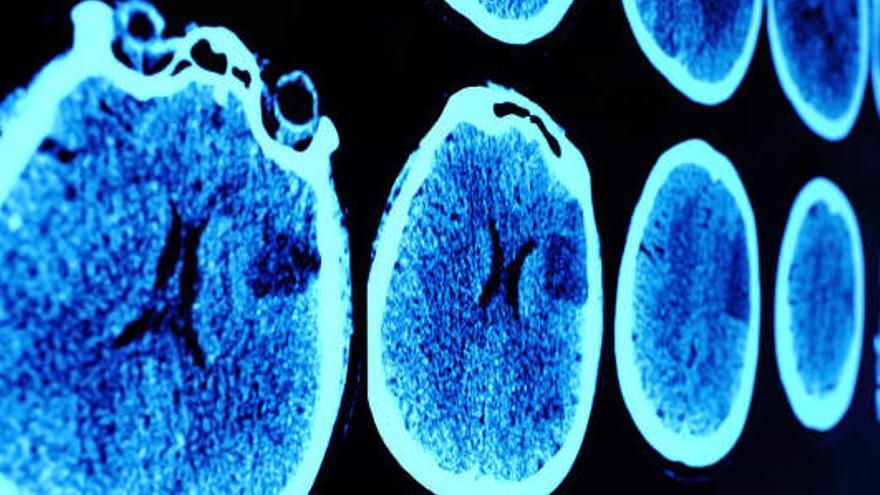

Els investigadors van explorar els efectes del bilingüisme sobre el volum i el metabolisme cerebral utilitzant tècniques de neuroimatge.

Així van veure que els pacients que al llarg de la seva vida han intercalat en més ocasions l'ús del català i el castellà tenen un millor rendiment cognitiu en determinades proves, més volum cerebral en zones frontals i un molt notable millor funcionament metabòlic en diferents zones frontotemporals i de l'escorça cingulada anterior dorsal.